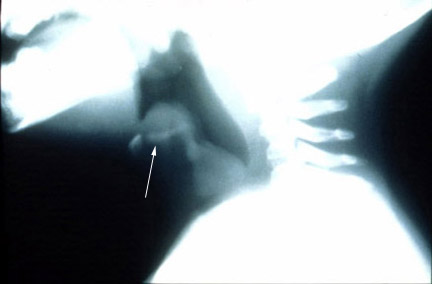

Lateral neck film illustrates normal epiglottis in profile.